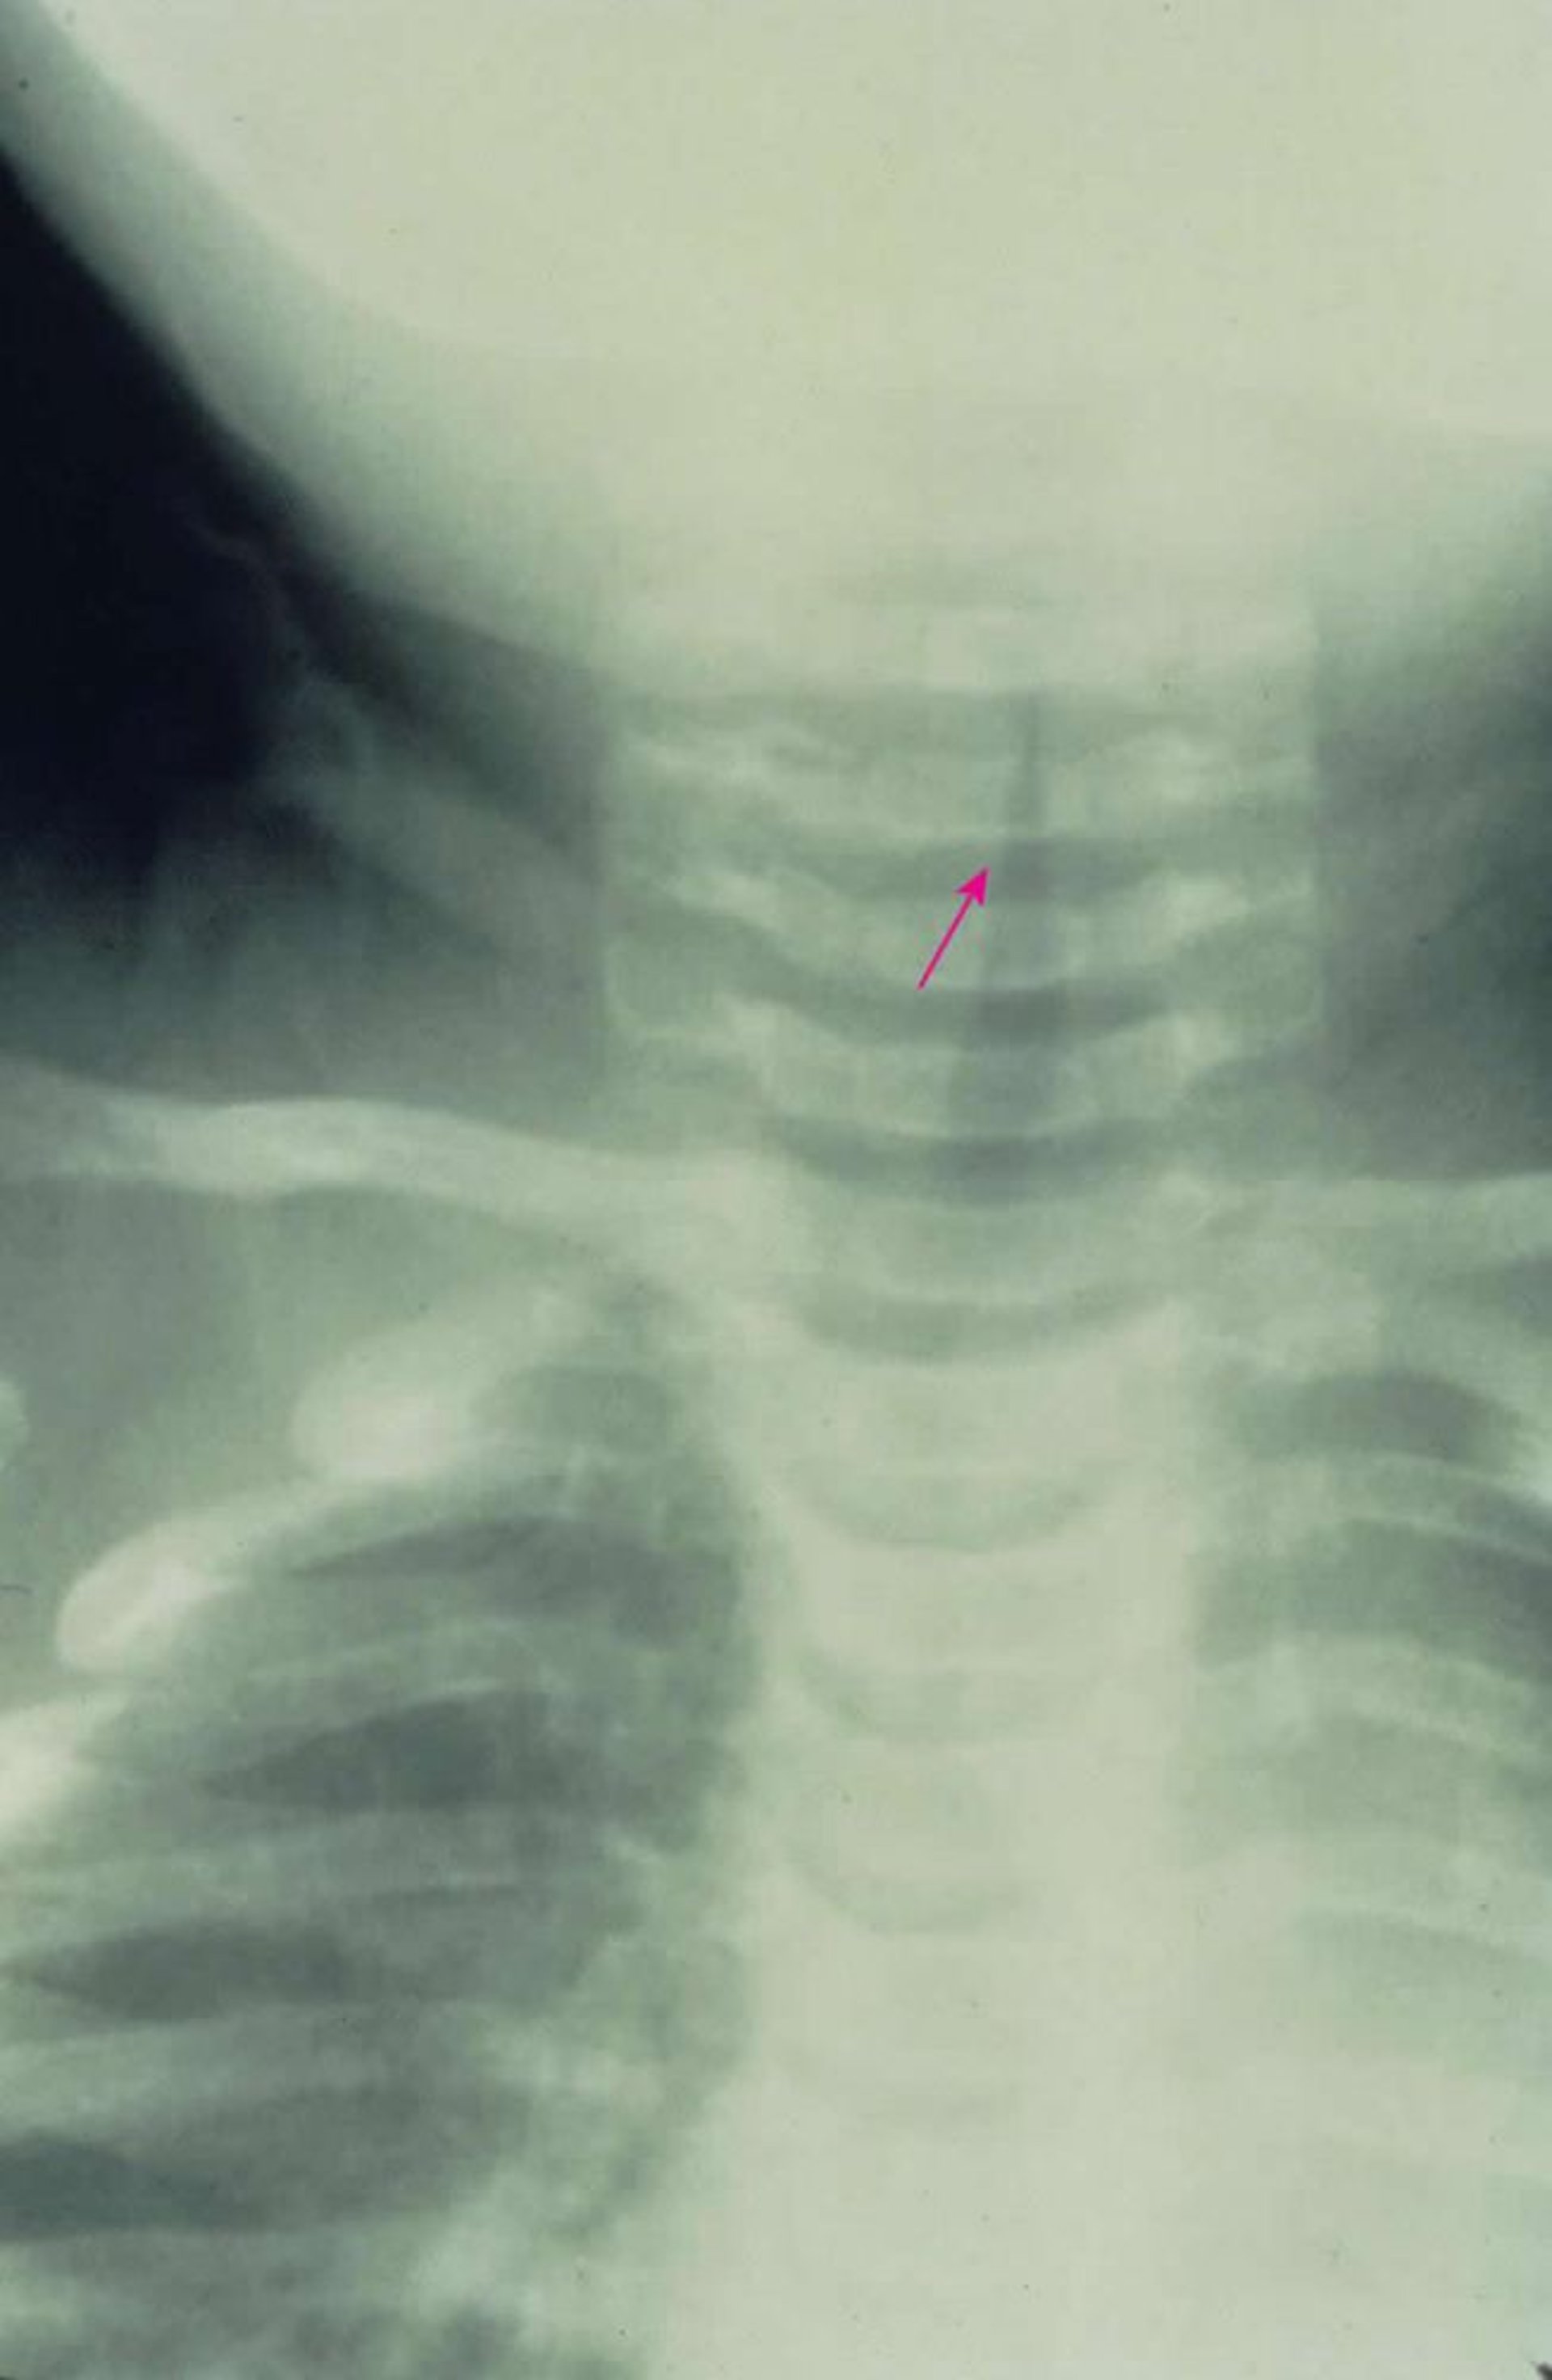

На рентгенограмме в прямой проекции видно характерное подсвязочное сужение дыхательных путей (конической формы[стрелка]), вызванное крупом.

Image provided by Clarence T. Sasaki, MD.